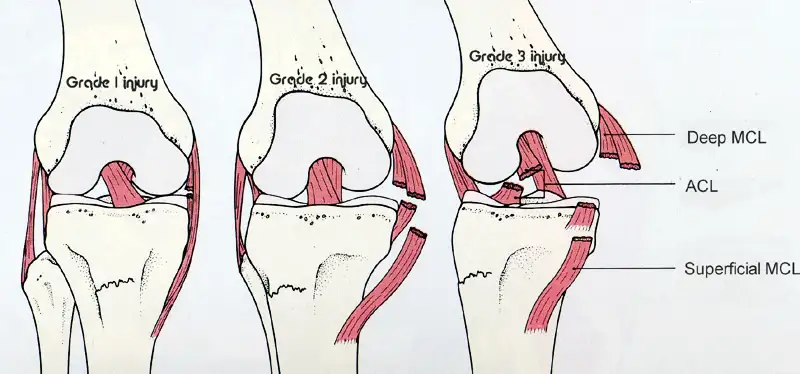

What is an MCL tear? It’s an injury that commonly occurs in athletes. Those who play high-impact sports like football or skiing are at higher risk. Direct blows to the knee or twisting can cause the ligament to stretch or tear. As a result, several MCL tear symptoms may appear.

MCL tear signs and symptoms often include: – Localized pain on the inner side of the knee. – Swelling around the MCL tear swelling location, which is generally inside the knee. – A feeling of instability or weakness, making the knee buckle under pressure.

If you suspect an MCL tear, getting a correct diagnosis is key. Medical experts usually start with a physical exam. They’ll check your knee’s stability and note any MCL tear swelling location. Imaging tests like X-rays or MRIs are used to see the inside of your knee clearly.